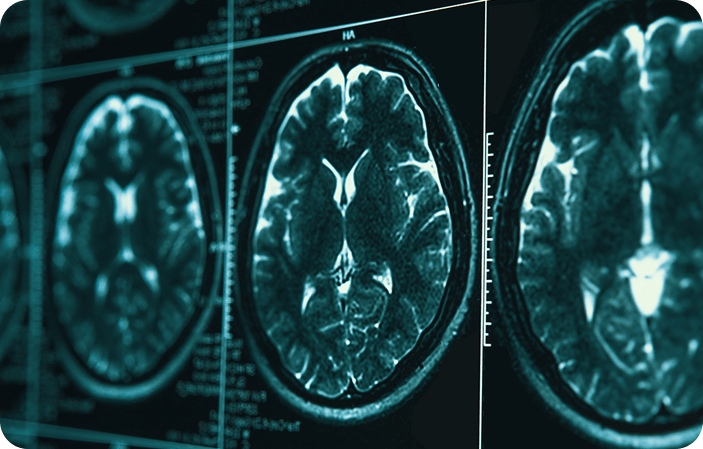

脳神経内科は脳、脊髄、神経を担当する診療科です。認知症を中心とする変性疾患、パーキンソン病、てんかんを診療しています。必要に応じて専門施設への紹介も可能ですので、お気軽にご相談ください。認知症専門医が在籍しており、認知症の診療に力を入れています。脳血管障害後遺症や高齢者のフレイルについても介護連携にて治療・リハビリを行っています。